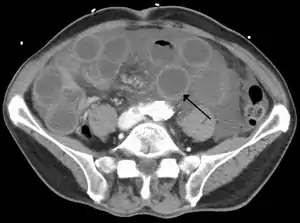

![]() КТ показує дилатовані петлі тонкого кишечника з потовщеними стінками (чорна стрілка), картина характерна для ішемії кишечника внаслідок тромбозу верньої брижової вени. КТ показує дилатовані петлі тонкого кишечника з потовщеними стінками (чорна стрілка), картина характерна для ішемії кишечника внаслідок тромбозу верньої брижової вени. | |